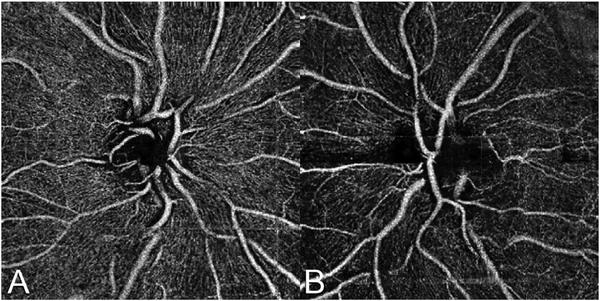

Optical coherence tomography (OCT) was one of the biggest advances in ophthalmic imaging. Building on that platform, OCT angiography (OCTA) provides depth resolved images of blood flow in the retina and choroid with levels of detail far exceeding that obtained with older forms of imaging. This new modality is challenging because of the need for new equipment and processing techniques, current limitations of imaging capability, and rapid advancements in both imaging and in our understanding of the imaging and applicable pathophysiology of the retina and choroid. These factors lead to a steep learning curve, even for those with a working understanding dye-based ocular angiography. All for a method of imaging that is a little more than 10 years old. This review begins with a historical account of the development of OCTA, and the methods used in OCTA, including signal processing, image generation, and display techniques. This forms the basis to understand what OCTA images show as well as how image artifacts arise. The anatomy and imaging of specific vascular layers of the eye are reviewed. The integration of OCTA in multimodal imaging in the evaluation of retinal vascular occlusive diseases, diabetic retinopathy, uveitis, inherited diseases, age-related macular degeneration, and disorders of the optic nerve is presented. OCTA is an exciting, disruptive technology. Its use is rapidly expanding in clinical practice as well as for research into the pathophysiology of diseases of the posterior pole.

光学相干断层扫描(OCT)是眼科成像领域的重大突破之一。在此基础上,OCT 血管造影术(OCTA)提供了视网膜和脉络膜血流的深度分辨图像,其细节水平远远超过了旧的成像方式。这种新的模式具有挑战性,因为需要新的设备和处理技术,目前成像能力的限制,以及成像和对视网膜和脉络膜成像及适用病理生理学的理解的快速发展。这些因素导致学习曲线陡峭,即使对于那些对基于染料的眼部血管造影术有一定了解的人来说也是如此。所有这些都是为了一种成像方法,它的历史还不到 10 年。这篇综述从 OCTA 的发展历史和 OCTA 中使用的方法开始,包括信号处理、图像生成和显示技术。这是理解 OCTA 图像显示内容以及图像伪影产生原因的基础。本文还回顾了眼部特定血管层的解剖结构和成像。介绍了 OCTA 在评估视网膜血管阻塞性疾病、糖尿病性视网膜病变、葡萄膜炎、遗传性疾病、年龄相关性黄斑变性和视神经疾病的多模态成像中的整合。OCTA 是一种令人兴奋的、颠覆性的技术。它在临床实践中的应用以及对后极部疾病病理生理学的研究中迅速扩展。